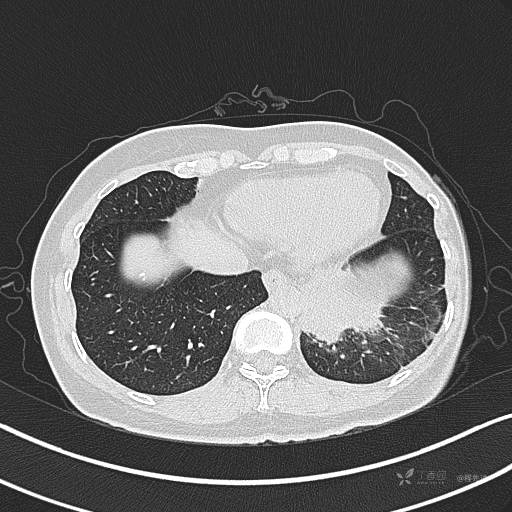

CT平扫

病灶平扫CT值约31HU

肺窗